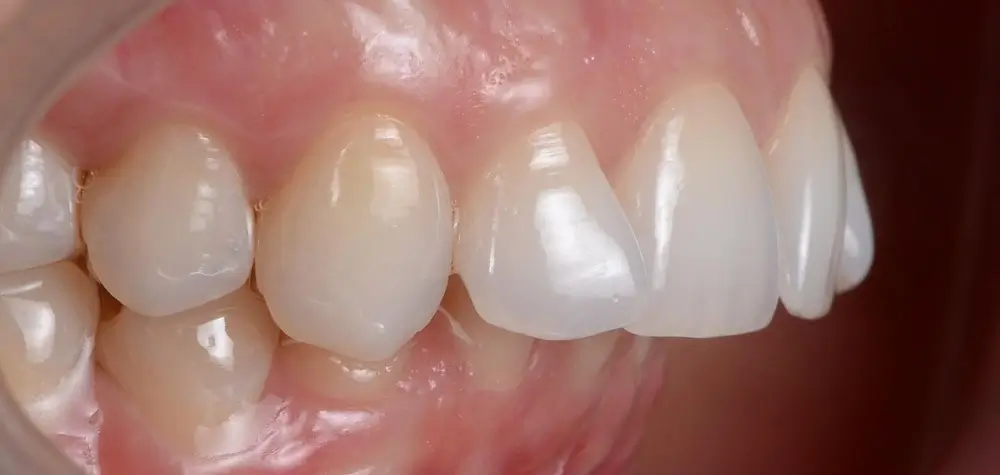

Дистальный прикус - Кейс 4

Эффективность устранения дефекта прикуса посредством элайнеров FlexiLigner.

Результаты лечения